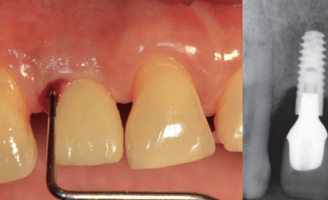

Tratamiento de enfermedades periimplantarias

Se refiere a la atención y manejo de enfermedades que afectan los tejidos alrededor de los implantes dentales, como la mucositis y la periimplantitis.

Manejo de mucositis periimplantaria

Se trata de la inflamación de los tejidos alrededor de un implante dental sin pérdida ósea significativa. Incluye limpieza y cuidado para evitar que la inflamación progrese a periimplantitis.

Tratamiento de periimplantitis

Es una infección que afecta los tejidos alrededor de un implante dental, causando pérdida ósea y posible fracaso del implante. El tratamiento incluye limpieza profunda y, en algunos casos, cirugía.

Mantenimiento de implantes dentales

Consiste en el seguimiento regular de los implantes dentales para asegurar su funcionamiento adecuado y prevenir problemas como la mucositis o la periimplantitis.